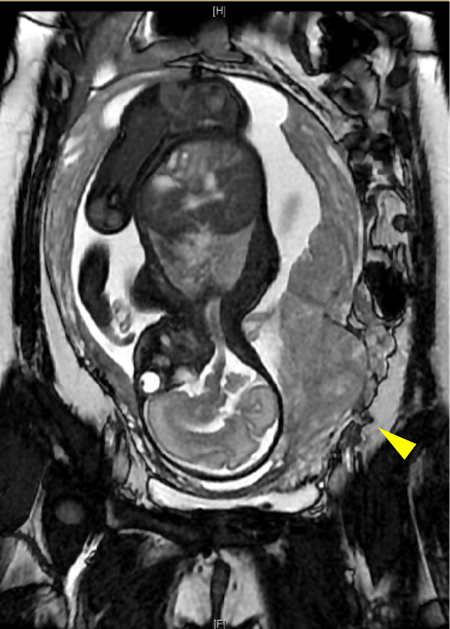

妇产科接力守护 MDT鼎力支持 宫颈与宫体横断患者终圆母亲梦

2021年12月15日,在北医三院产科、妇科、儿科、泌尿外科、介入血管外科、麻醉科以及ICU等科室专家团队通力合作下,一台特殊的剖宫产手术紧张而有序地进行。新生儿的啼哭和最终产妇平安返回病房,为这场为期3年的接力...